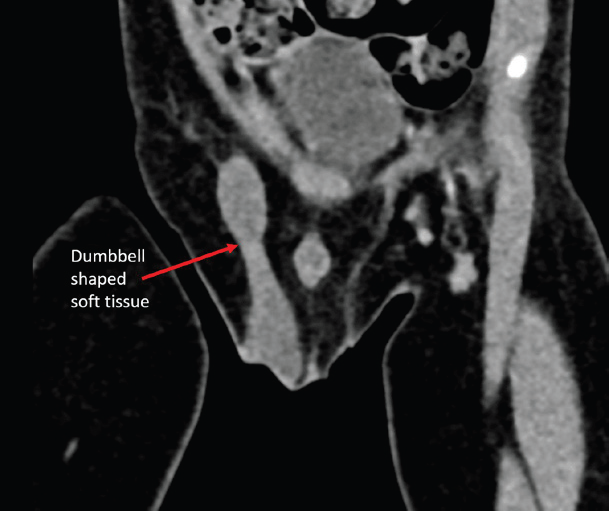

failed to identify the left testis. Contrast-enhanced CT (CECT) pelvis

revealed a dumbbell-shaped enhancing soft tissue density extending

from the right inguinal canal into the scrotum [Figure 1,2,3].

Figure 1: Oblique coronal reconstruction of CECT pelvis showing dumbbell shaped

homogeneously enhancing soft tissue density tracking into the right

scrotum.